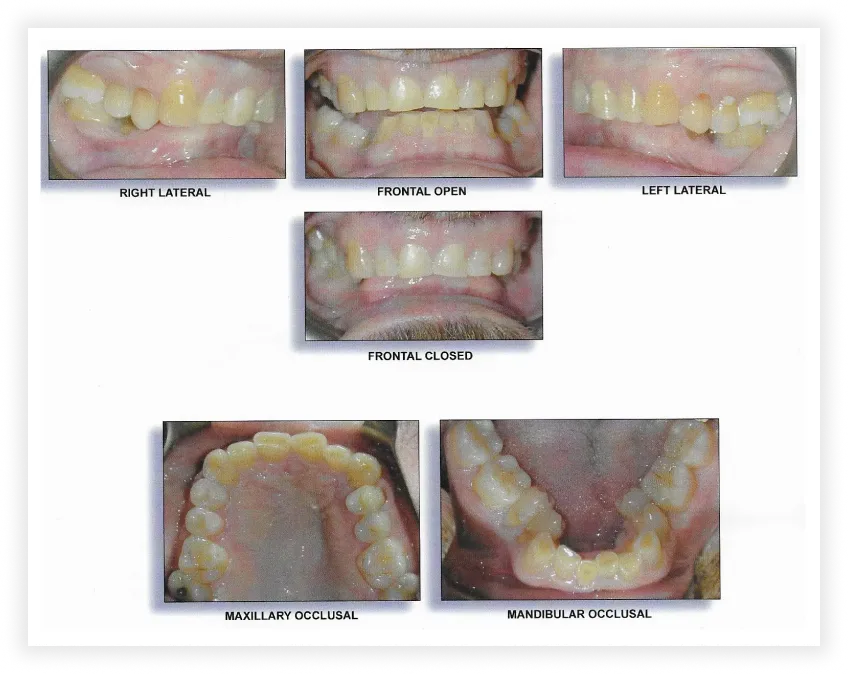

Smile Gallery

Take a look at some of our cases and successful transformations below.

Case #1

Initial Photos